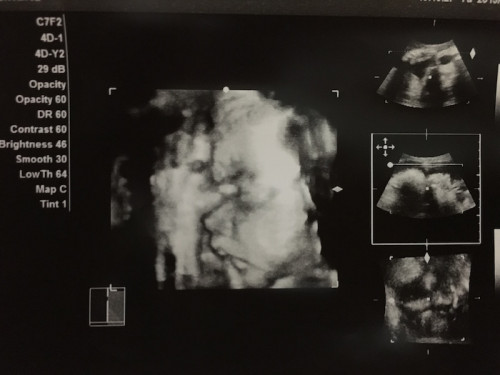

こちらは1人目の時の3Dエコーの画像。手と横顔の様子がはっきりわかります。

3Dや4Dに対応した超音波診断装置を導入している産院も増えています。お腹の赤ちゃんが大きくなりすぎるとうまく撮影できなくなるため、3D、4D撮影は28週頃までにおこなってもらうといいですよ。